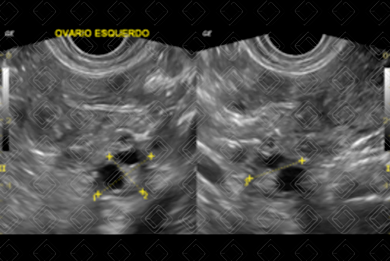

Texto alternativo para a imagem Figura 7. Créditos: Dra. Elazir Mota - Rio de Janeiro/RJ

Texto alternativo para a imagem Figura 8. Créditos: Dra. Elazir Mota - Rio de Janeiro/RJ

Texto alternativo para a imagem Figura 9. Créditos: Dra. Elazir Mota - Rio de Janeiro/RJ

Descrição das figuras 7, 8 e 9: Paciente de 35 anos, feminina. Ultrassonografia da pelve, estudo via transvaginal, evidenciando lesão hipoecoica, com ecos internos em suspensão e discretos nódulos hiperecogênicos parietais, sem fluxo ao Doppler colorido, sugerindo endometrioma (seta vermelha); lesão foi ressecada e seu diagnóstico confirmado.

Endometrioma (figuras 7, 8 e 9): Na ultrassonografia, são lesões císticas hipoecoicas, habitualmente homogêneas, com finos ecos internos e pequenos focos ecogênicos parietais (vale ressaltar que não deve haver vascularização nestes pequenos nódulos).